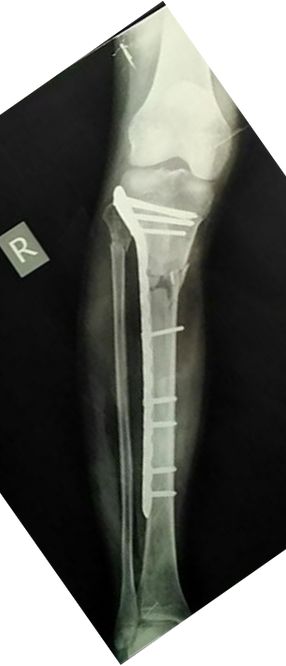

经验与教训:胫骨干骺端骨折皮下传钢板,力线有些差,内翻,但可以接受。伤口感染,如果简单换药引流也无大碍。结果用双氧水冲洗后造成肌肉坏死,胫前肌腱坏死,骨坏死外露,处理困难。最后结果还希望原作者上传,大家共同接受教训。